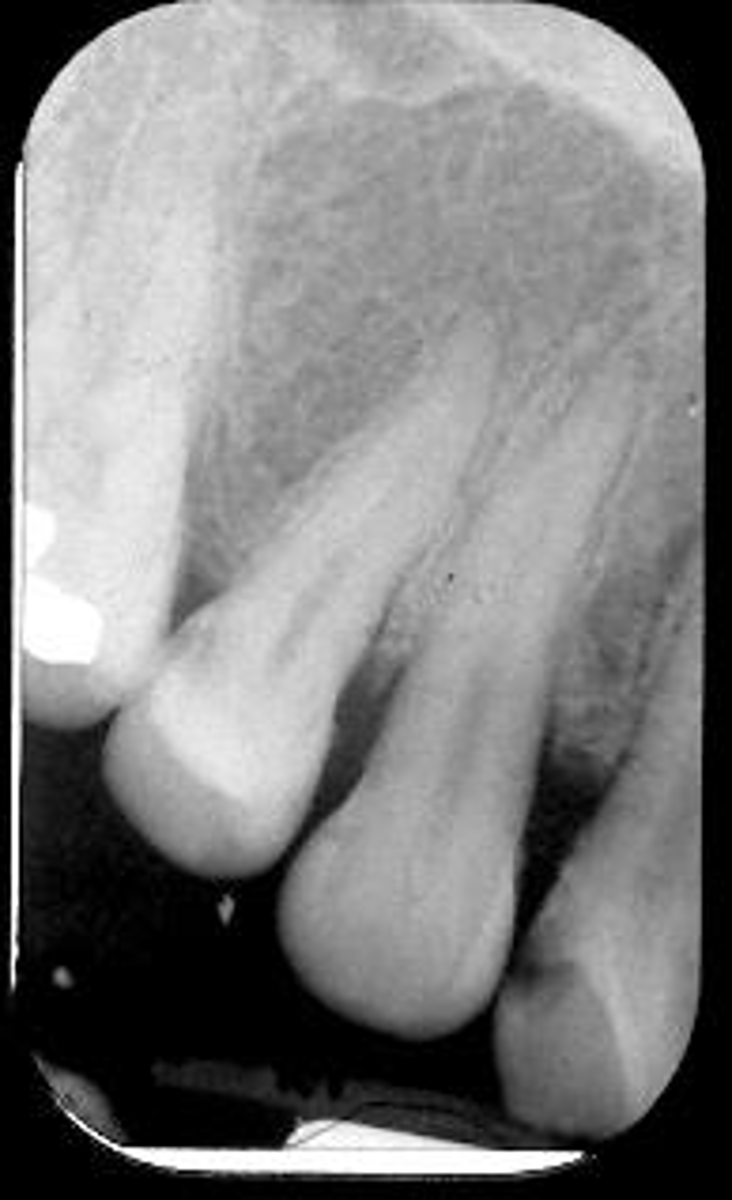

Patient is not biting down

What is this error?